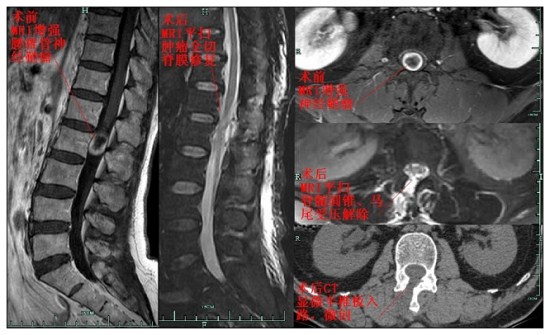

我院神将外科已独立开展的显微镜下经微创半椎板入路手术,已熟练用于治疗各种椎管病变。近一月来已收治三例病人,一例82岁高龄女性患者因双下肢麻木、乏力逐渐进展入院,经MRI检查确诊为胸椎管腹侧脊膜瘤,手术难度大;一例合并椎管囊肿的腰椎间盘突出症的患者;一例腰椎管大型神经鞘瘤的患者。三名患者均行显微镜下微创半椎板入路手术,病变完整切除,无手术并发症,术后三天即下地自由活动,手术效果优,现均已康复出院。微创手术解除了疾病给病人带来的痛苦,让他们能微笑迎接明天。